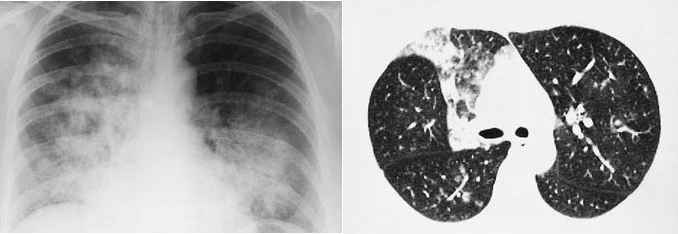

In general a CT scan is much better at finding lung

cancers than a chest Xray (see

CT Scans: chest Xray versus CT, chest Xray versus CT,

Xray versus CT, CT small left lung nodule, CT